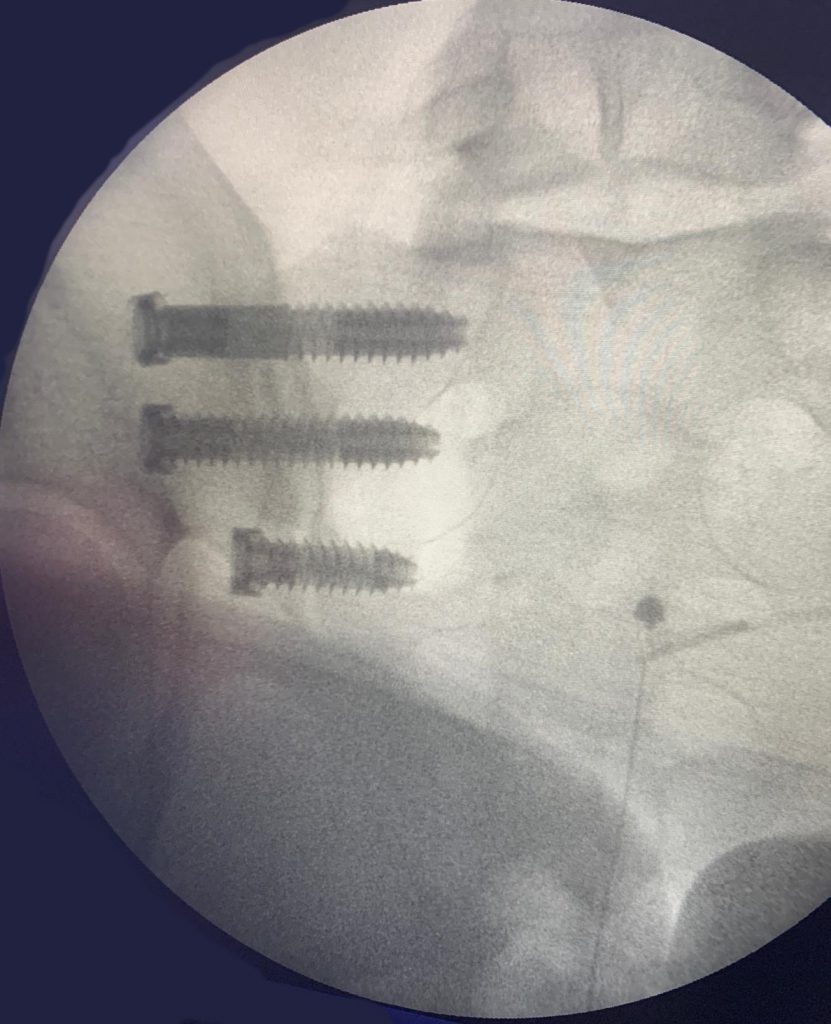

Las intervenciones realizadas, fusión o artrodesis sacroilíaca abierta, conlleva la fusión de ambos huesos. Para ello, se realiza una cicatriz a nivel lumbar y se colocan tornillos entre el sacro y el ilíaco añadiéndose injerto óseo.